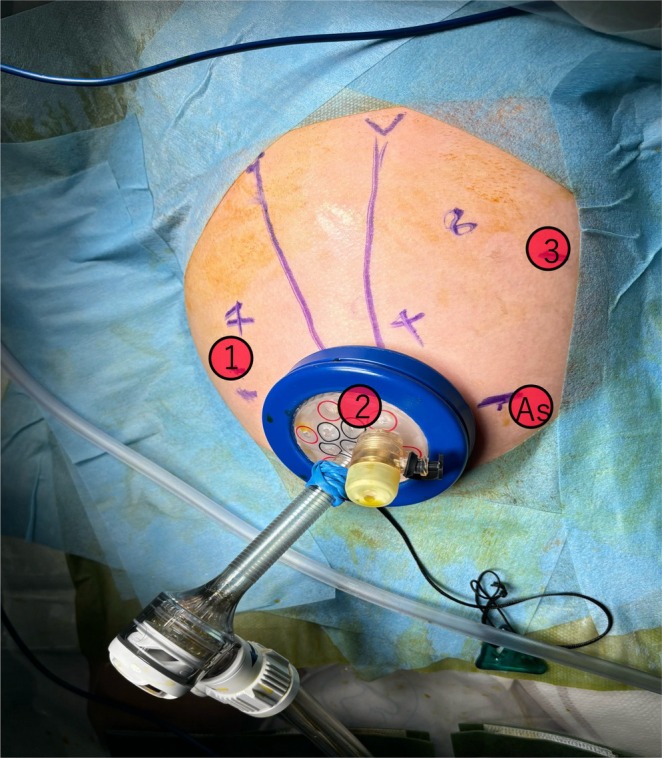

Fresh frozen plasma was administered to correct coagulopathy immediately after admission, and the patient underwent emergency robotic surgery using the da Vinci Xi surgical system 6 h later. A Benz incision was made at the umbilicus to insert a multichannel port with additional robotic ports placed, following our conventional approach [ref. 4] (Figure 2). Bile‐stained ascitic fluid was observed. The hepatoduodenal ligament was inflamed and adhered to adjacent structures, including the duodenum, colon, and greater omentum. Initial adhesiolysis was performed laparoscopically, followed by robotic docking (Supporting Information: Video). Dissection of the common bile duct revealed a perforation on its anterior wall. The distal bile duct was mobilized into the pancreas without difficulty. Intraoperative cholangiography revealed a protein plug in the common channel with poor contrast passage into the duodenum, which improved after repeated irrigation (Figure 3). The bile duct was transected approximately 5 mm proximal to the common channel junction. Proximal dissection up to the hepatic hilum revealed no strictures. The right hepatic artery runs anterior to the common hepatic duct; the duct was successfully mobilized anteriorly to this vessel. A Roux‐en‐Y jejunal limb was prepared via an umbilical incision, and hepaticojejunostomy was completed robotically using 5–0 absorbable monofilament sutures with single knots via retrocolic route. A drain was placed behind the anastomotic site.